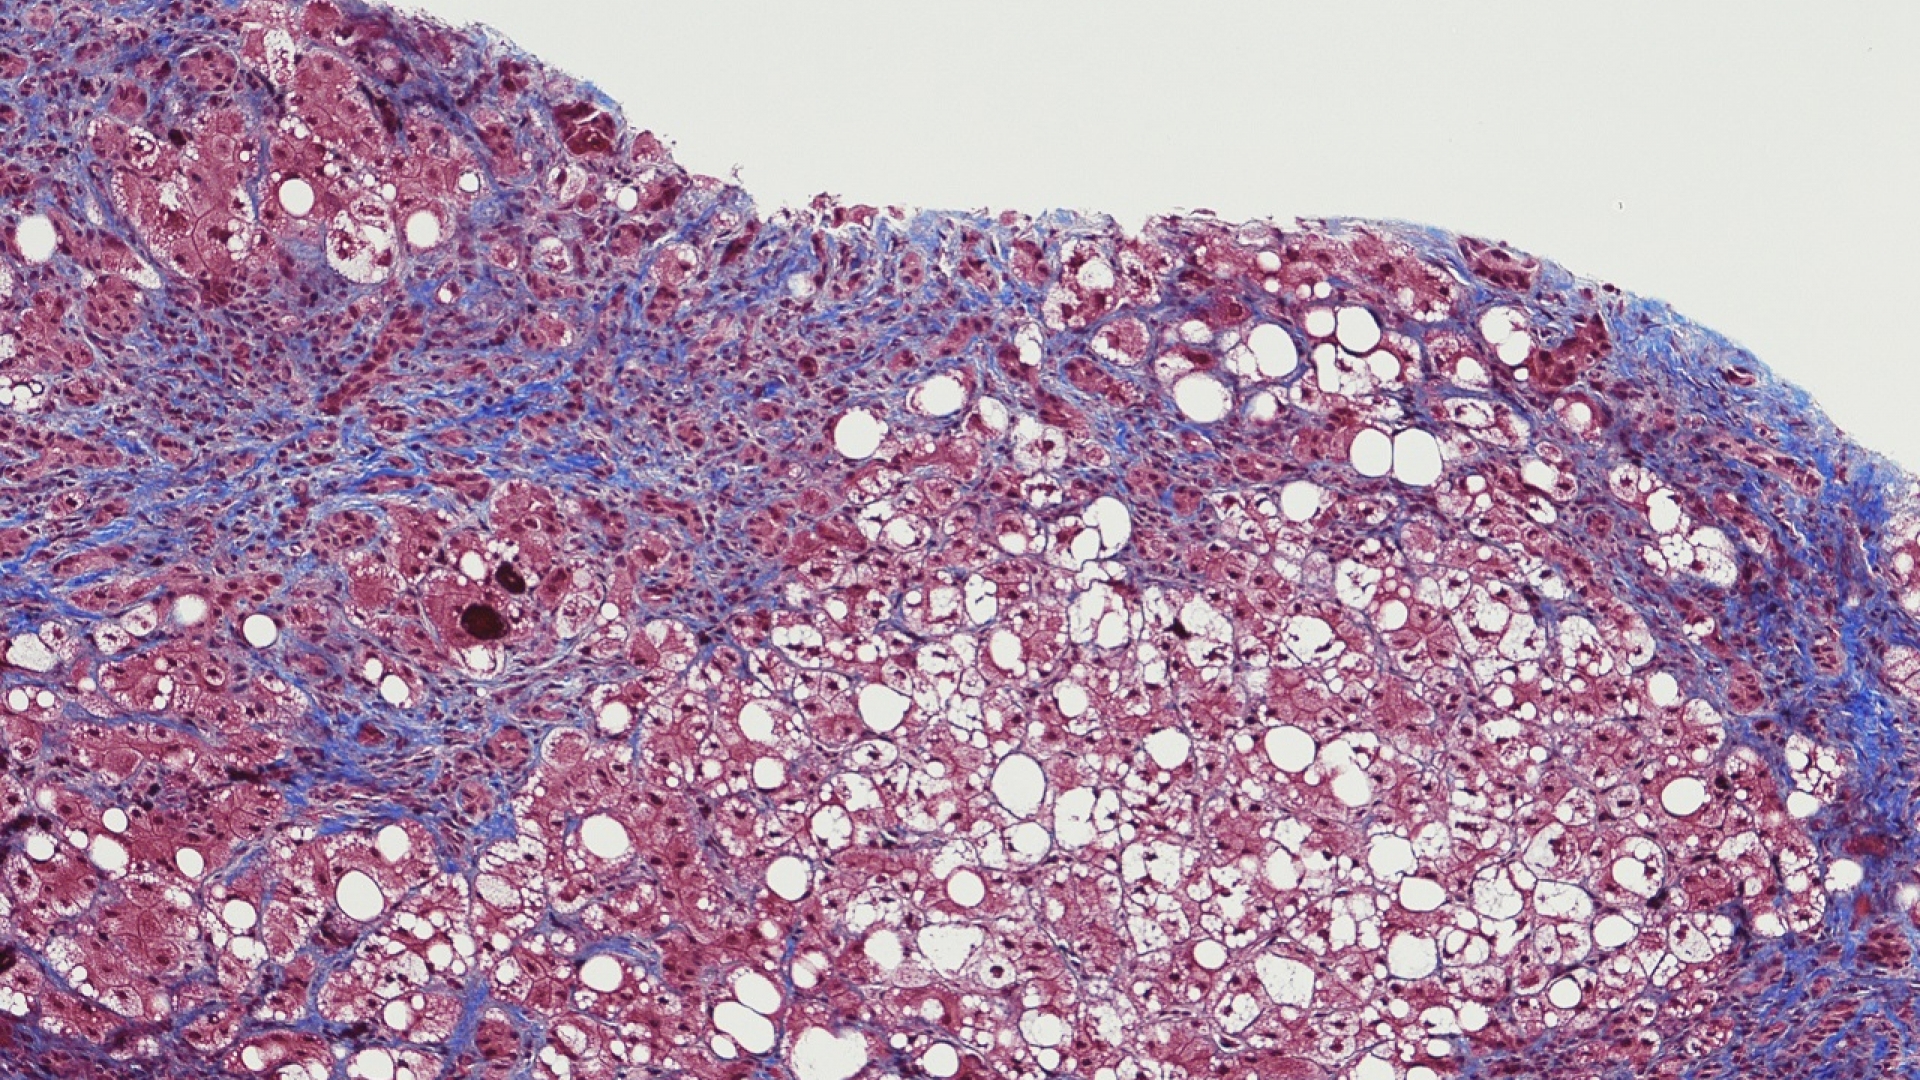

Zu den möglichen Langzeitfolgen einer Hepatitis C zählt die Entwicklung einer Leberzirrhose.

"Hepatitis C kann zu Leberzirrhose und Leberzellkrebs führen und eine Organtransplantation erforderlich machen. Es ist daher ganz wichtig, dass wir diese Erkrankung frühzeitig erkennen und behandeln", erklärt Manns. Möglich ist dies dank neuer Therapien, mit denen mehr als 90 Prozent aller Betroffenen geheilt werden können.